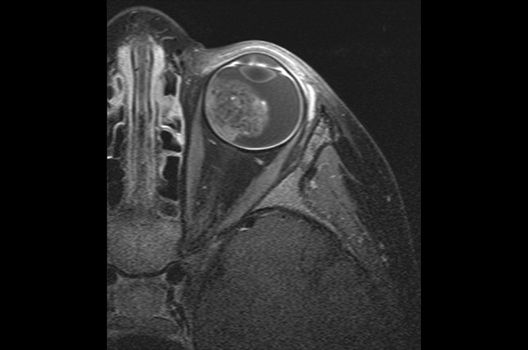

Die Schwerpunkte in der MR-Forschung liegen in der multiparametrischen und funktionellen Bildgebung bei onkologischen und anderen, neuroradiologischen Fragestellungen und umfassen die Anwendung modernster MR-Verfahren sowie die Untersuchung an Hochfeld-Geräten.

Die Magnetresonanztomographie (MRT) ist ein Verfahren, bei dem durch magnetische Kräfte Bilder des Körperinneren angefertigt werden. In der Neuroradiologie können manchmal kleinste Veränderungen schwere Folgen haben; daher forschen wir an der Entwicklung hochauflösender MRT-Sequenzen, mit denen diese Prozesse und auch einzelne Nervenfaserbahnen sichtbar gemacht werden können. Darüber hinaus sind bei vielen Erkrankungen des Gehirns die Blutgefäße betroffen. Daher arbeiten wir an der Neu- und Weiterentwicklung von MRT-Sequenzen zur Darstellung der Blutgefäße und zur Blutflussanalyse (sog. „Angio-MRT“). Einen besonderen Forschungsschwerpunkt unserer Klinik stellen die MR-Protonenspektroskopie und die funktionelle MRT dar, mit denen die Analyse einzelner chemischer Substanzen im Hirngewebe oder die Darstellung ausgewählter Hirnfunktionen möglich ist.